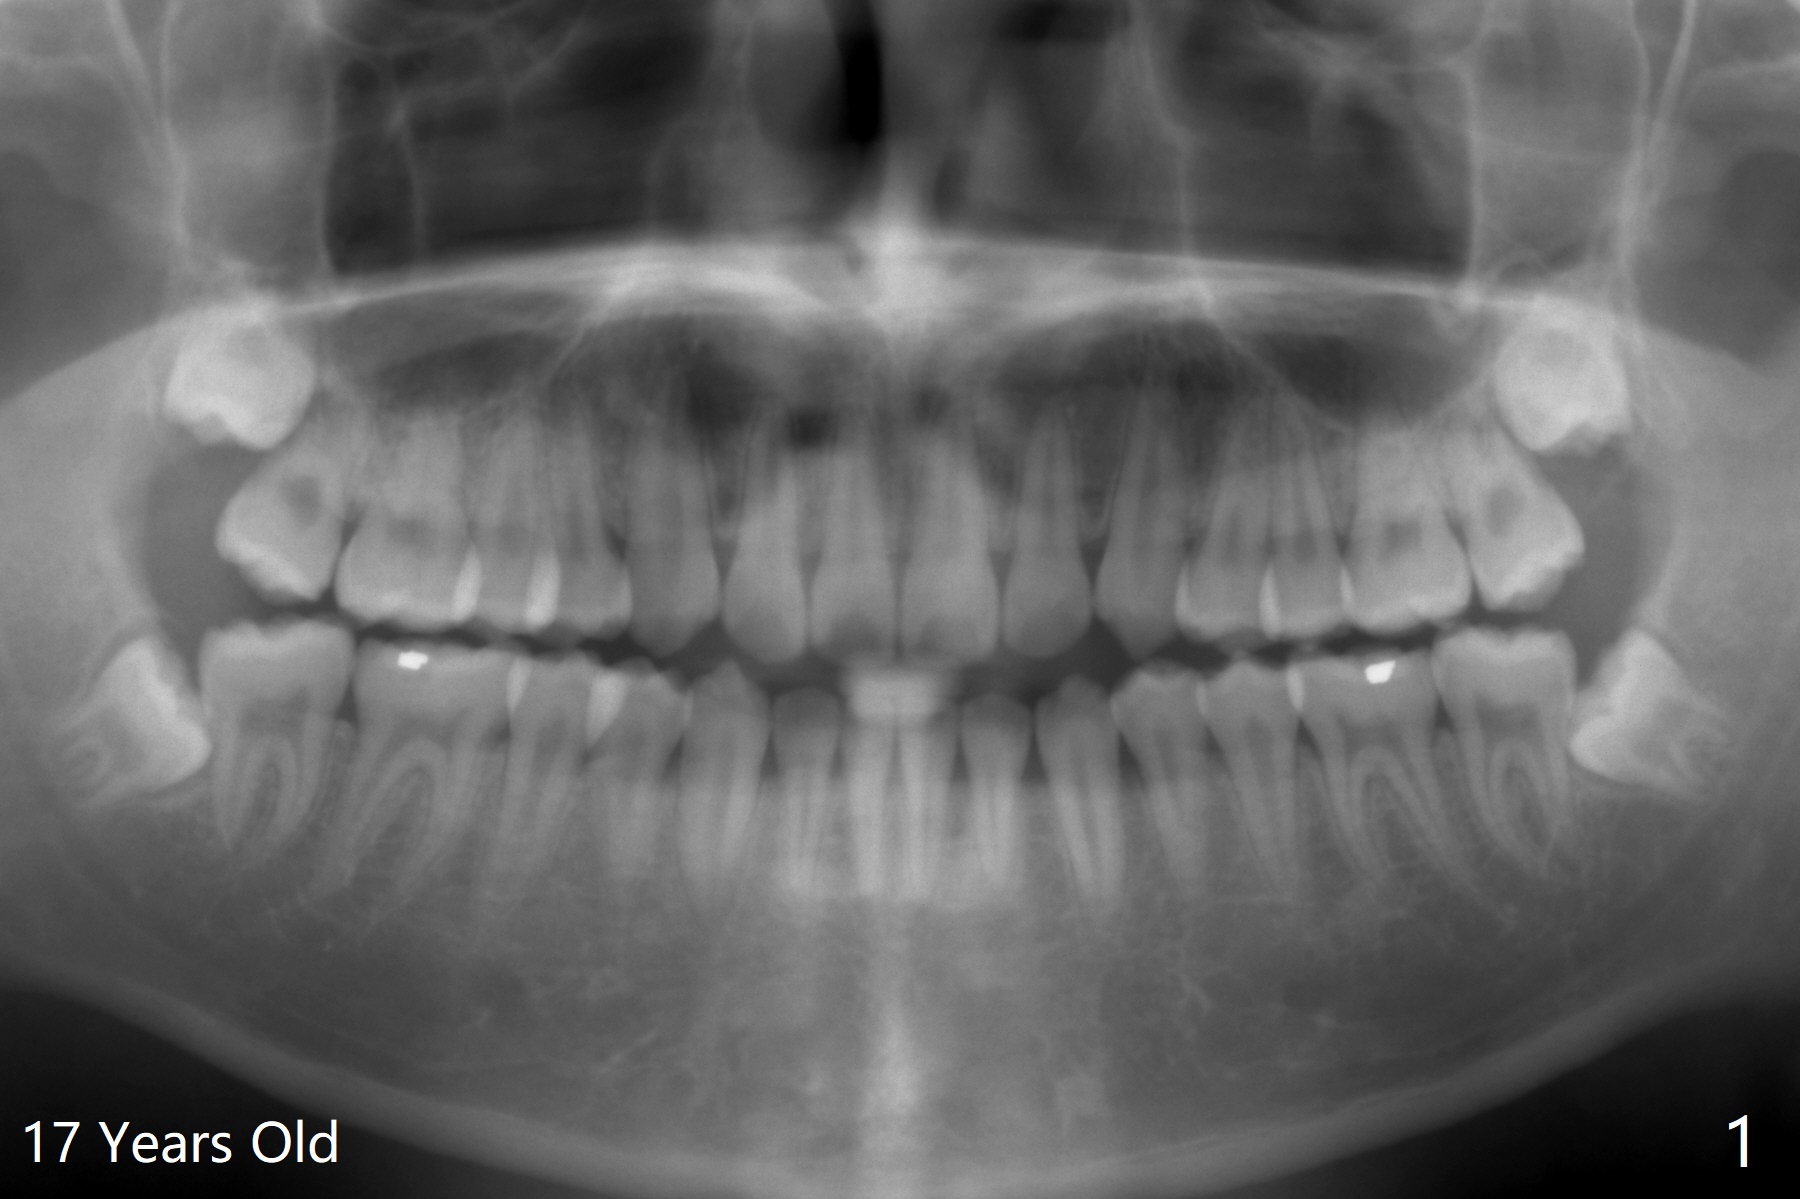

A 21-year-old man returns to clinic with pain and swelling at #17 (Fig.1,2). After multiple sectioning, the tooth is extracted with insertion of collagen plug post extraction in the late afternoon. The patient complains of sharp pain during local anesthetic injection. Postop paresthesia is gradually getting better, but gets worse 2 months postop (Fig.3,4). Neurotin is prescribed. Vitamin B1 and B12 are recommended. OMFS is suggested. 21岁男因左下智齿肿痛要求拔除(图一,二),术中发现轻度颊侧阻生,使用一只利多卡因,一只Septocaine,一般前者block anesthesia,后者infiltration。多次用手机切割牙齿,拔除后牙槽窝放置一个胶原塞(减少术后干槽症),4-0铬羊肠线缝合。术后两个月病人突然回来,主诉局麻注射造成剧痛,术后下嘴唇麻木开始逐渐好转,最近麻木突然加重(图三,四)。左下智齿牙槽窝已经愈合。处方:Neurotin;推荐维生素B1, B12;建议口外会诊。还能做什么?